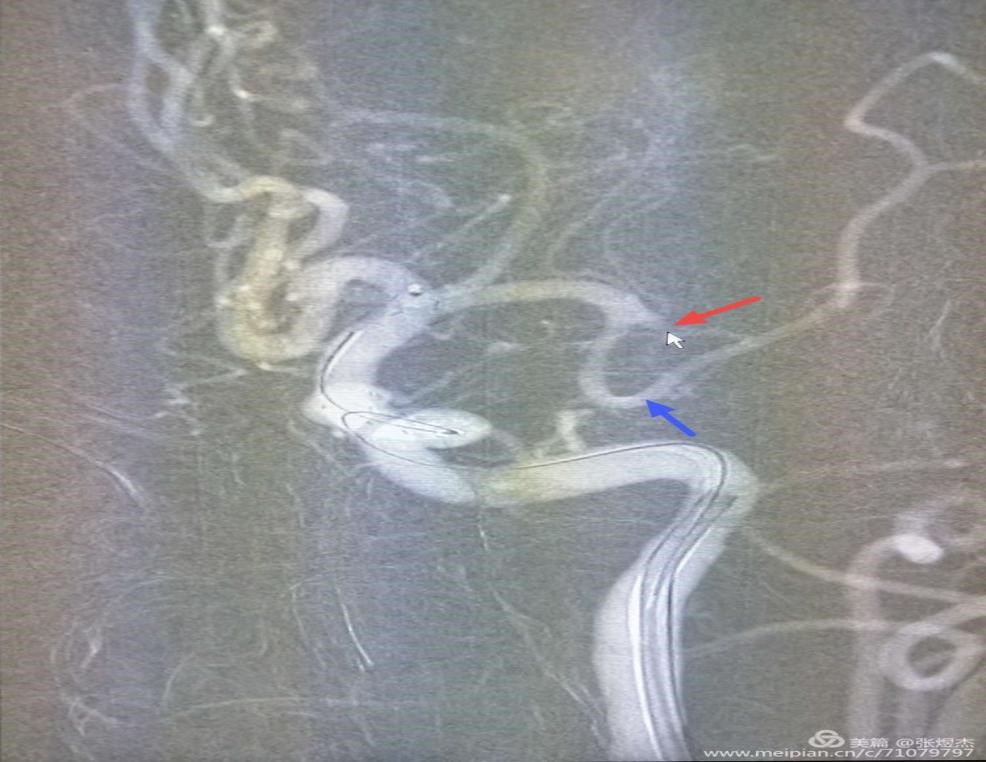

通过路径图的显示,将微导丝、微导管到达闭塞血管的近端,下一步就需要导丝突破闭塞的血管,这是一处关键步骤,因为闭塞以远的血管血流中断,是没有路径图显示的,图片中蓝色箭头指示的是通畅的下干血管一直向上延续,红色箭头指示的是闭塞的上干血管远端没有显影。

所以既要突破闭塞段,又要保证导丝头端在远端血管腔内,术者的指尖功夫,也就圈内人说的“活”得好啊。大家看下面这两幅图红箭头所指的导丝位置,上幅是顺应血管的走行,下幅只是抬高了10°就已经是穿出血管外了。正所谓差之毫厘、失之千里,等待术者的就只剩下从缺血到出血的冰与火的考验了。

随着导丝顺利通过闭塞段血管,沿导丝引入微导管至远端血管,造影证实导管在真腔内,远端血管显影,栓子也正是卡在这个拐弯的位置。